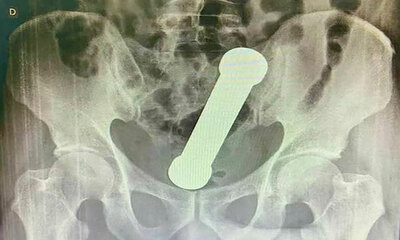

Un homme se coince un haltère de 2 kilos dans l’anus

Au Brésil, un homme de 53 ans adepte du DBSM a mis un haltère de 2 kilogrammes et 20 centimètres dans son anus. Il a passé deux jours avec l'haltère dans le cul, mais s’est rendu chez le médecin que lorsqu'il s'est rendu...